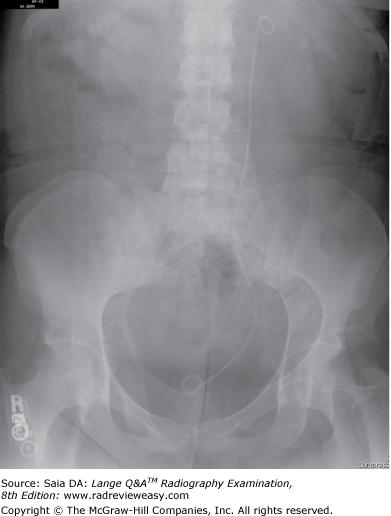

The radiograph seen below illustrates incorrect use of

A collimator

B grid

C AEC

D focal spot

-An upside-down focused grid presents its lead strips in the opposite direction to that of the x-ray beam. This results in severe grid cutoff everywhere except in the central portion of the radiographic image. Severe grid cutoff of chest anatomy can be seen outside the central exposed area. A misaligned collimator would not show such symmetrical loss of receptor exposure, nor would an incorrectly selected AEC photocell. Focal spot is unrelated to receptor exposure.